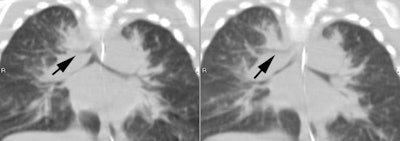

Pig bronchus (black arrow): Neonate with persistent intermittent RUL atelectasis |